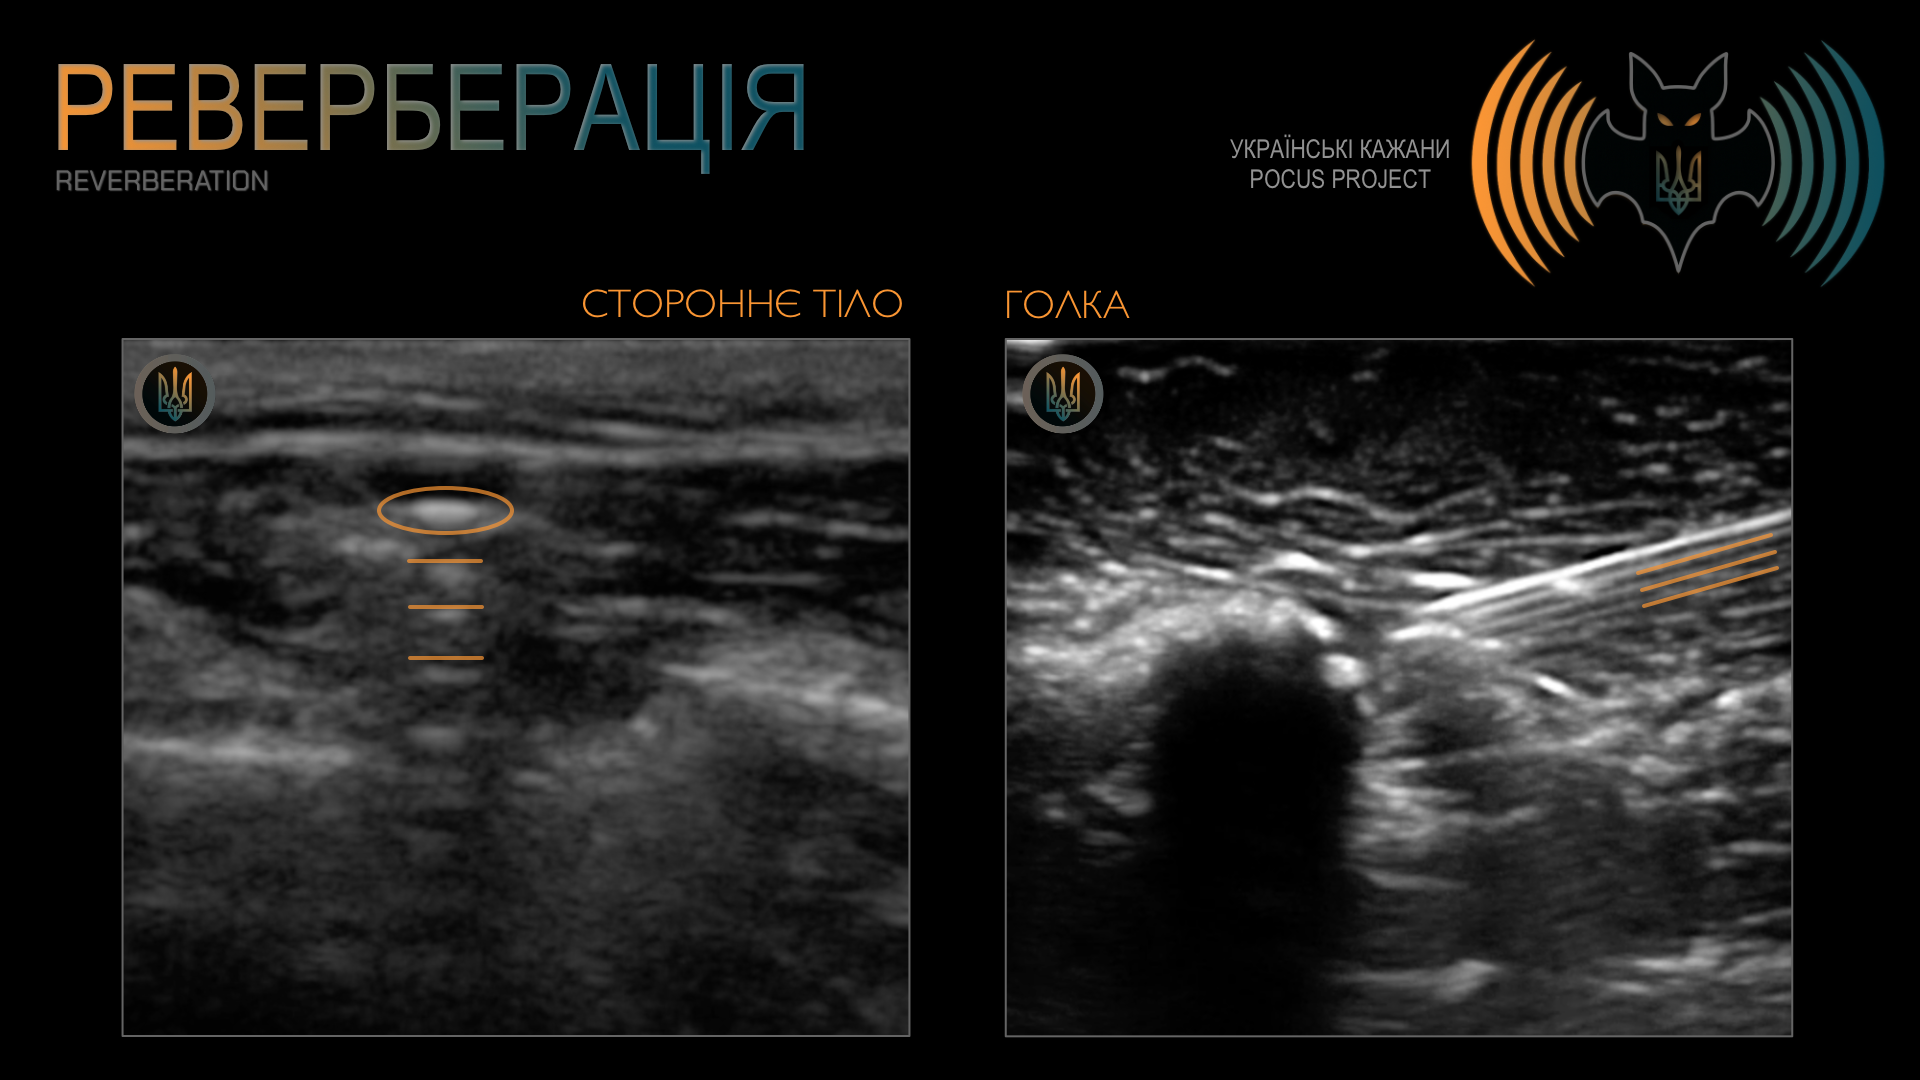

РЕВЕРБЕРАЦІЯ: ще один поширений артефакт, який виникає тоді, коли УЗ-сигнал багаторазово відбивається між двома сильними відбивачами. У результаті на екрані з’являється характерна «сходинкоподібна» картина з паралельних ехо-сигналів. Ми часто спостерігаємо цей артефакт в УЗД легені (A-лінії є паралельними відбиттями плеври). Водночас реверберацію можна використовувати й на нашу користь — наприклад, під час локалізації сторонніх тіл або виконання процедур під УЗ-контролем.